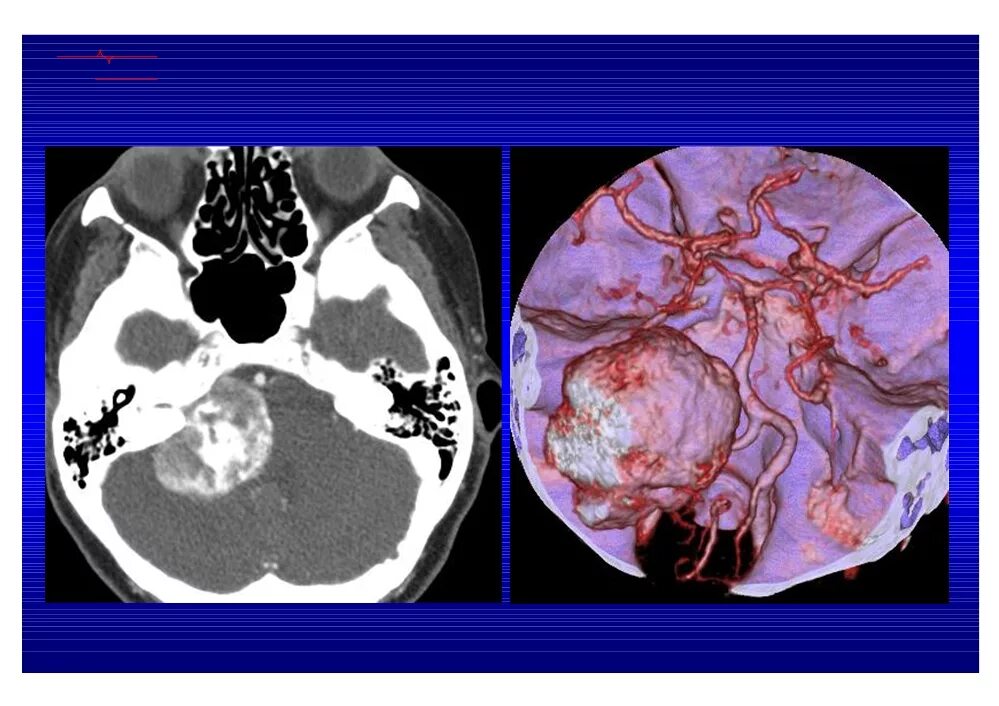

Мрт головного мозга мосто мозжечкового угла